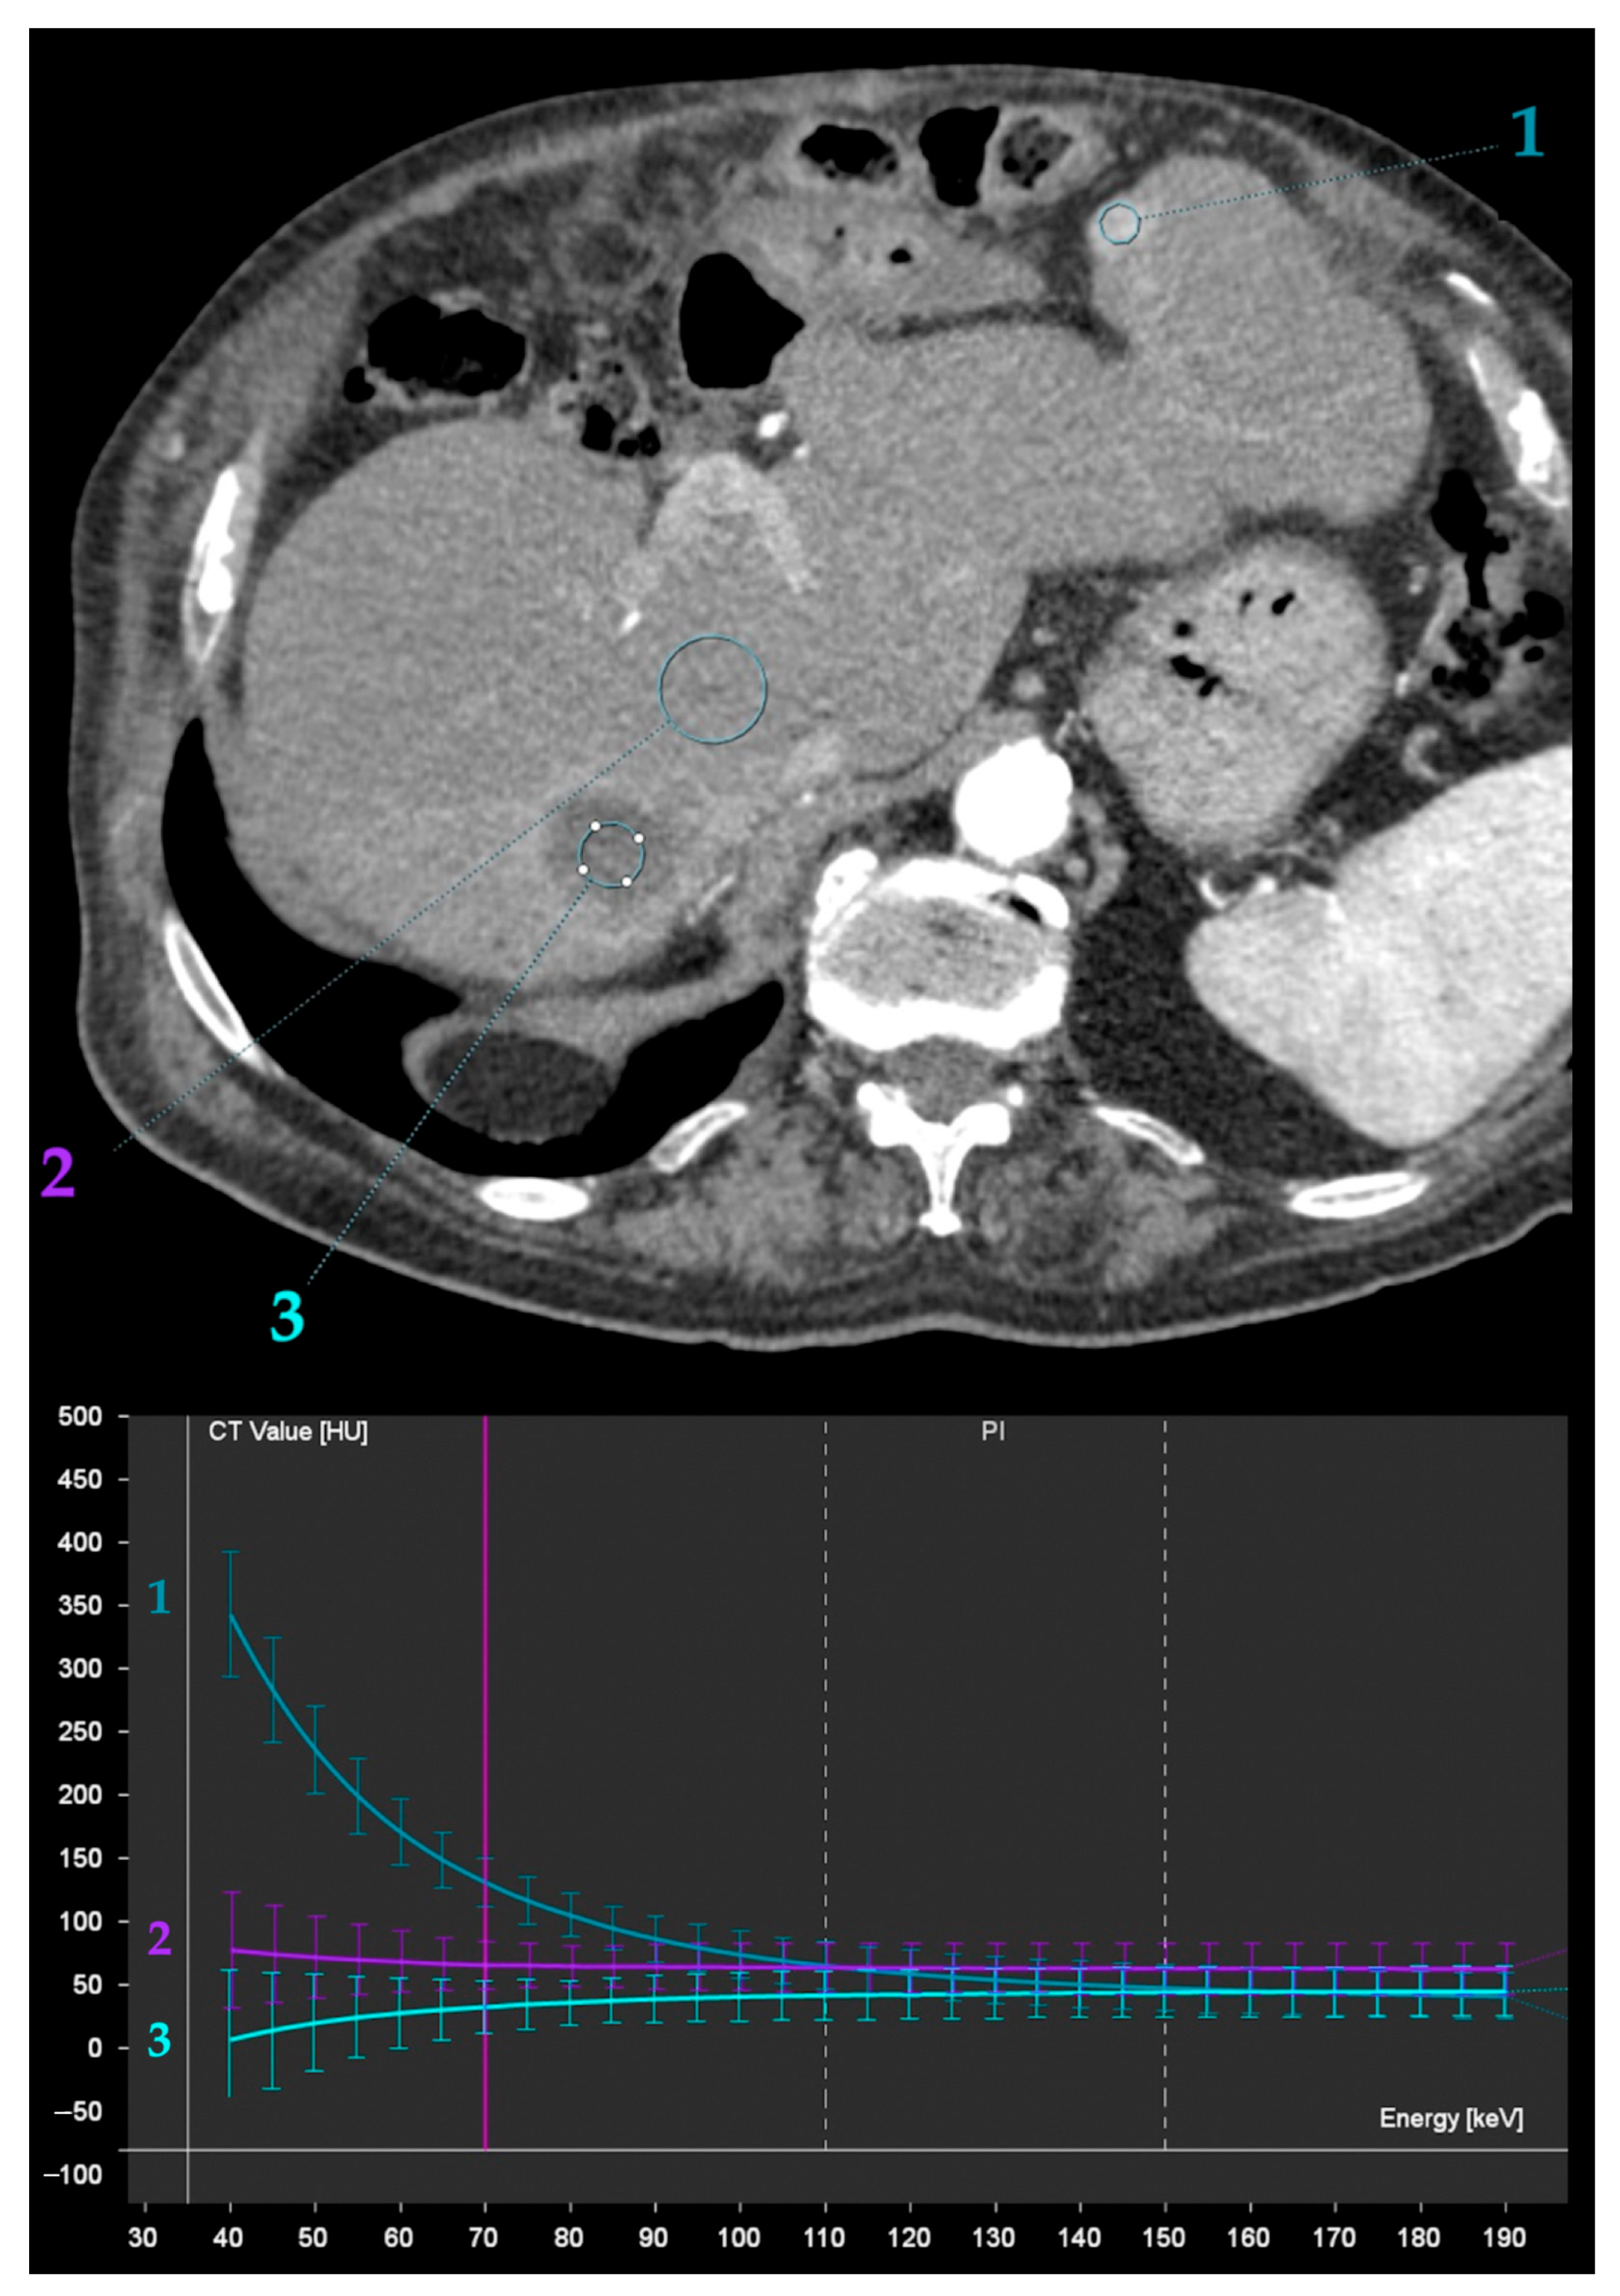

- Wang, Q.; Shi, G.; Qi, X.; Fan, X.; Wang, L. Quantitative analysis of the dual-energy CT virtual spectral curve for focal liver lesions characterization. Eur. J. Radiol. 2014, 83, 1759–1764. [Google Scholar] [CrossRef]